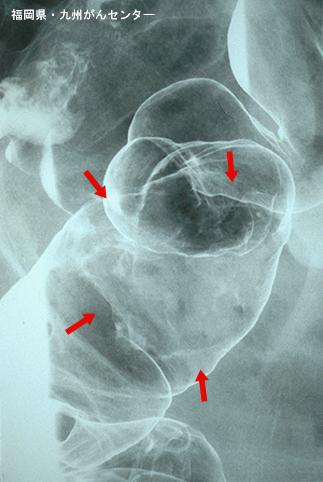

症例提示(所在地,施設名等): 福岡県・ 九州がんセンター

疾患(病理主体)の分類悪性上皮性腫瘍/腺癌

部位(臓器別)大腸/S状

検査方法X-P

腫瘍の肉眼分類1型(腫瘤型)/

病変の最大径(ミリ)40以上

腫瘍の深達度ss(a1)